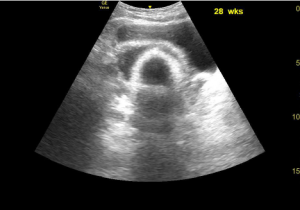

Pelvic ultrasound of a female who is 28 weeks pregnant.